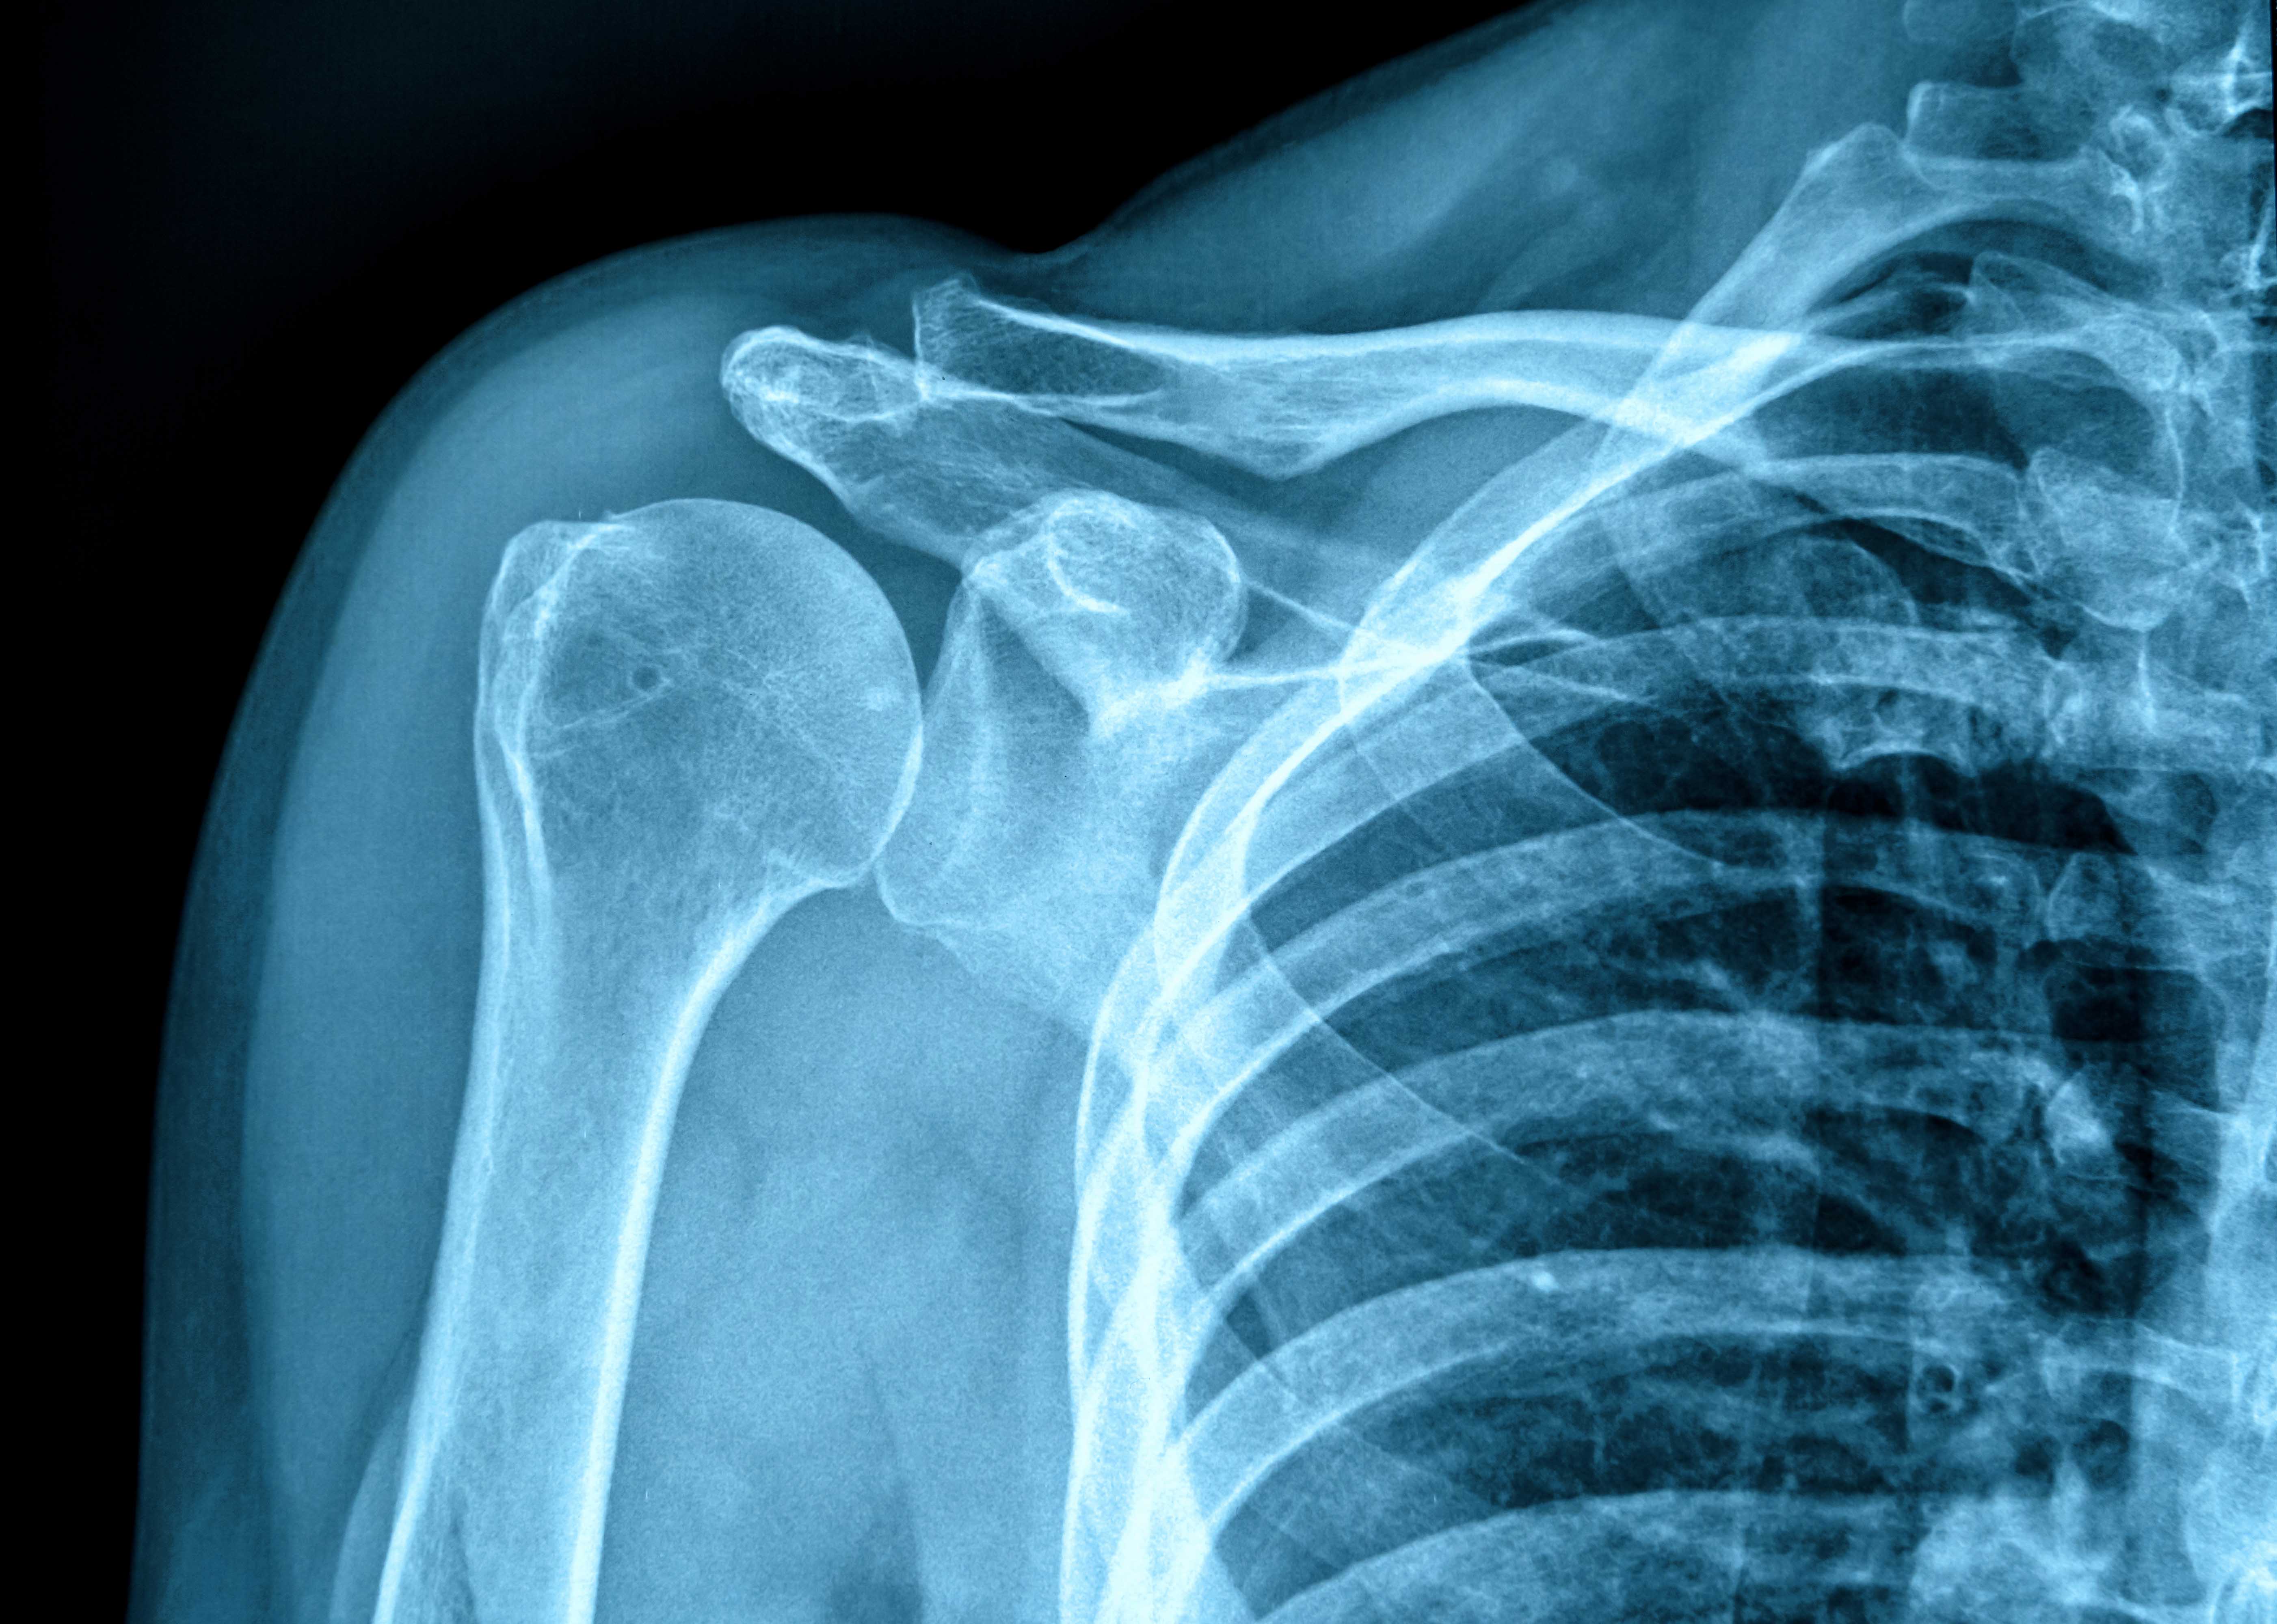

يمتد برنامج زمالة تصوير الجسم بالأشعة على مدار عام واحد يكتسب المتدرب خلاله الخبرة في جميع أوجه التصوير بالأشعة لمنطقة البطن والحوض لدى الكبار، مثل الأشعة فوق الصوتية (ويتضمن ذلك الفحوصات معززة التباين)، والمنظار الفلوري، والأشعة المقطعية، والرنين المغناطيسي. ويتم بشكل منتظم إجراء الأشعة المقطعية التشخيصية وتصوير الأوعية بالرنين المغناطيسي بالإضافة إلى أحدث الدراسات مثل تصوير القولون بالأشعة المقطعية وكذلك فحوصات أشعة الرنين المغناطيسي، باستخدام عوامل تباين خاصة بأنسجة معينة. ويتم التركيز بشدة على إعادة التشكيل ثلاثي الأبعاد والمعالجة اللاحقة.